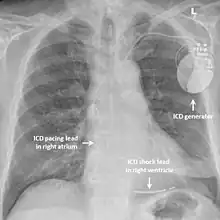

The risk of arrhythmias may be reduced by taking beta blockers such as propranolol; however, the evidence for this is poor as of 2013.[4] Other antiarrhythmic drugs such as flecainide and verapamil may also be helpful.[4] Those at highest risk of recurrent arrhythmias such as those who have already had a cardiac arrest may benefit from an implantable cardioverter defibrillator – a small device implanted under the skin which can detect dangerous arrhythmias and automatically treat them with a small electric shock.[4]